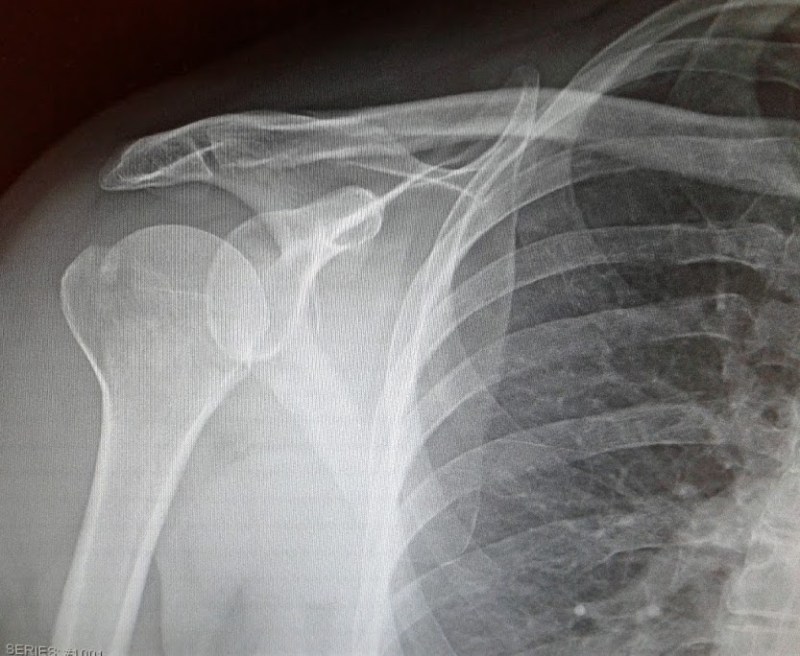

John has tagged several of my exercises to help me remember them and probably also to make me laugh. Humor helps when you’re stretching and strengthening muscles after a right shoulder break. It takes the edge off the pain.

This recovery takes time, effort and grit. I certainly don’t feel like a woman of leisure as I recline, hands behind head with elbows bent stretching muscles. That right elbow won’t flex down like my left. And I feel pain.

But I’m getting there. After days of washing windows—placing my hands on a hand towel and sliding them up a wall—and other exercises, John noted that I was “significantly better” than at our previous visit. Three sessions into physical therapy, that encouraged me.